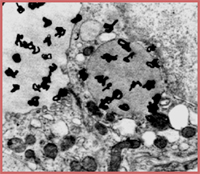

用放射自顯影能夠研究的任何細胞特徵或抗原物質定位也可以用放射自顯影和免疫染色聯合進行研究。特別之處是同時進行抗原定位研究,操作過程直截了當。細胞用適當的方法進行放射性標記,接著進行固定和按所選用的免疫染色法進行染色(注意:此時樣品和洗滌後的溶液應該作為放射性物品處理)。然後對細胞樣品進行放射自顯影,可以同時進行顯影銀粒和免疫染色觀察。

放射自顯影與免疫染色聯合套用最常用於研究DNA合成與抗原定位表達之間的關係。這時細胞用3H_TdR標記後,進行免疫染色和放射自顯影。這個方法能夠敏感而精確地研究正在進行DNA合成的細胞中抗原表達的位置。儘管如此,一般情況下建議用雙標記法進行這類研究,在細胞培養基中加入BrdU標記新合成的DNA,接著用2種不同顏色染料標記的抗體按上述雙標記法進行細胞染色,其中抗體之一是針對BrdU的抗體(已經商品化),而另一種抗體是針對所研究的抗原。